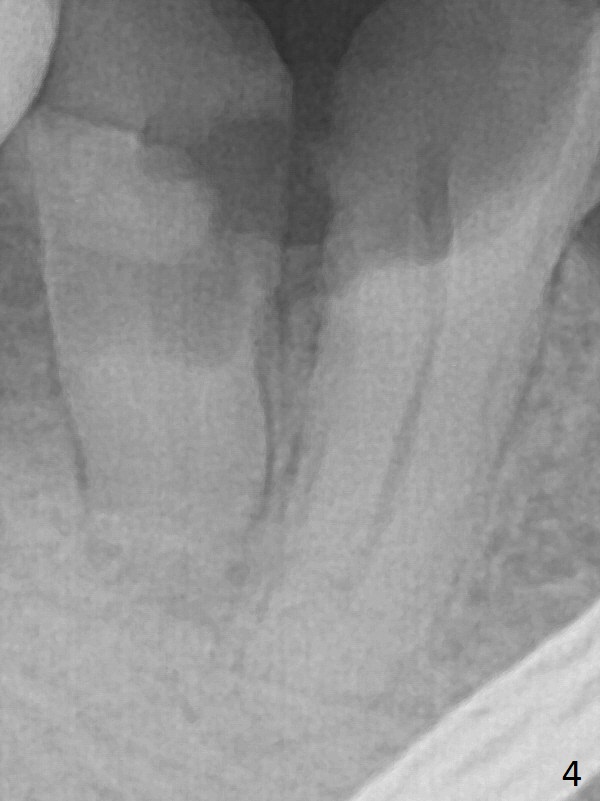

A 43-year-old man has residual roots at #30 (Fig.1). The mesial (M) and distal (D) roots approximates each other so close that the septum is thin (Fig.1,3-5). The latter is unfavorable for osteotomy. After extraction (Fig.5), the middle of the septum (Fig.8a (axial section of the sockets)) will be sectioned (Fig.6, 8b,c) prior to initial osteotomy (Fig.7,8d). The depth of the latter will be ~ 5 mm (Fig.2 red line) for a 13 mm (pink line) IBS implant.